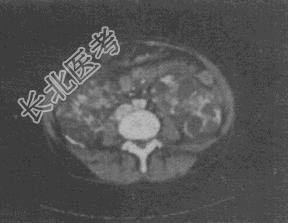

- 单项选择题男,56岁, 腹部包块伴高血压,CT扫描如图所示, 下列说法错误的是

A、双肾体积明显增大

B、双肾内可见多个大小不等的囊性病灶,呈蜂窝状改变

C、肝内可见多个大小不等的囊性病灶

D、考虑为多囊肾、多囊肝

E、考虑为双肾多发单纯性囊肿